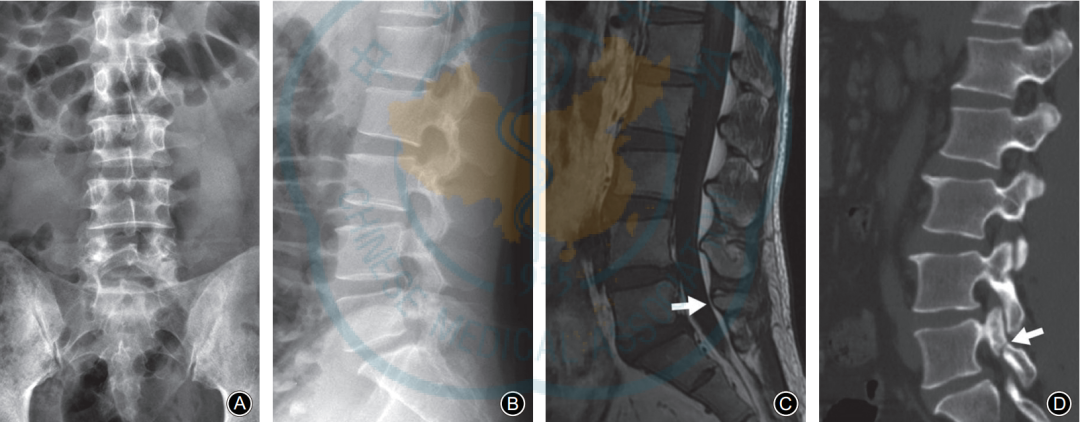

L5椎弓峡部裂典型病例一:男,32岁。A,B: 腰椎正位侧位X线片示无明显椎弓峡部裂征象; C: 腰椎 MRI正中矢状面T1WI示L5棘突基底部与硬膜之间出现脂肪高信号带(箭头示); D: 腰椎CT矢状面重建示L5椎弓峡部骨质不连(箭头示)。

L5椎弓峡部裂典型病例二:男,35岁。A,B: 腰椎正位侧位X线片均无明显椎弓峡部裂征象; C: 腰椎MRI正中矢状面T1WI示L5棘突基底部与硬膜之间出现脂肪高信号带(箭头示); D: 腰椎CT矢状面重建示L5椎弓峡部骨质不连,裂隙较细(箭头示)。